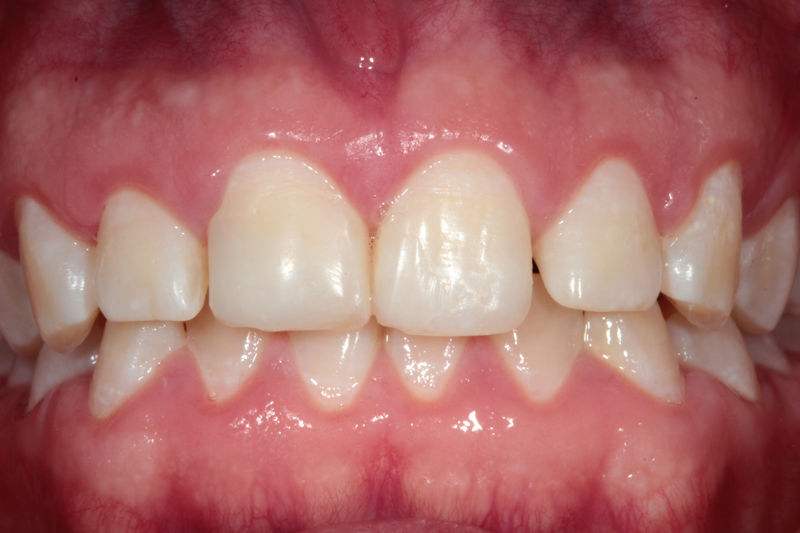

Amplia gama de tratamientos para mejorar la apariencia de la sonrisa, corrigiendo el color, la forma, el tamaño, la alineación y la posición de los dientes. Los procedimientos más comunes y solicitados incluyen el blanqueamiento dental, las carillas y coronas, así como las resinas.

Son restauraciones que cubren toda la cara frontal del diente, generalmente empleadas en el sector anterior y cuya finalidad es primariamente estética.

Son restauraciones con materiales plásticos color diente usados primariamente en dientes con caries pequeñas y puestas directamente en el diente.